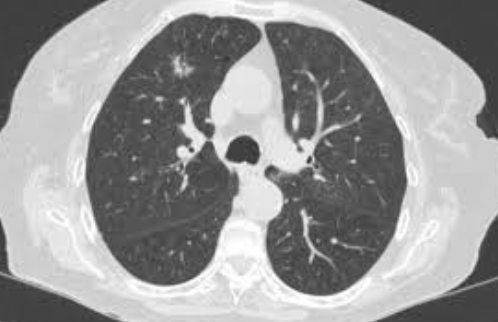

'폐결절이란' 폐 안에서 발견되는 작고 둥근 모양의 음영이나 덩어리를 말합니다. 보통 건강검진에서 흉부 CT나 X-ray를 통해 우연히 발견되는 경우가 많죠. 대부분은 3cm 이하의 크기를 가지며, 크기가 작을수록 양성(즉, 암이 아닌 경우)일 가능성이 높다고 알려져 있습니다.

- 고해상도 CT(컴퓨터단층촬영): 결절의 크기와 형태, 경계, 석회화 여부 등을 더 정밀하게 관찰

실제로 저도 고해상도 CT를 한 번 더 찍은 뒤, 결절의 변화 여부를 확인하기 위해 6개월 후 재검을 권유받았습니다. 매일매일 불안하게 기다리는 건 아니었지만, 가끔 생각날 때마다 마음이 무거웠던 건 사실이에요. 하지만 의사 선생님이 "작고, 경계가 뚜렷하며, 모양이 균일한 경우 대부분은 문제가 없다"고 말씀해주셔서 많이 안심됐습니다.